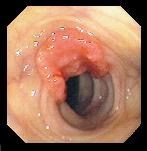

Ce que l'on observe lors d'une coloscopie

![]() |

Rectum et

début du colon sigmoïde |

Cancer du Colon

|